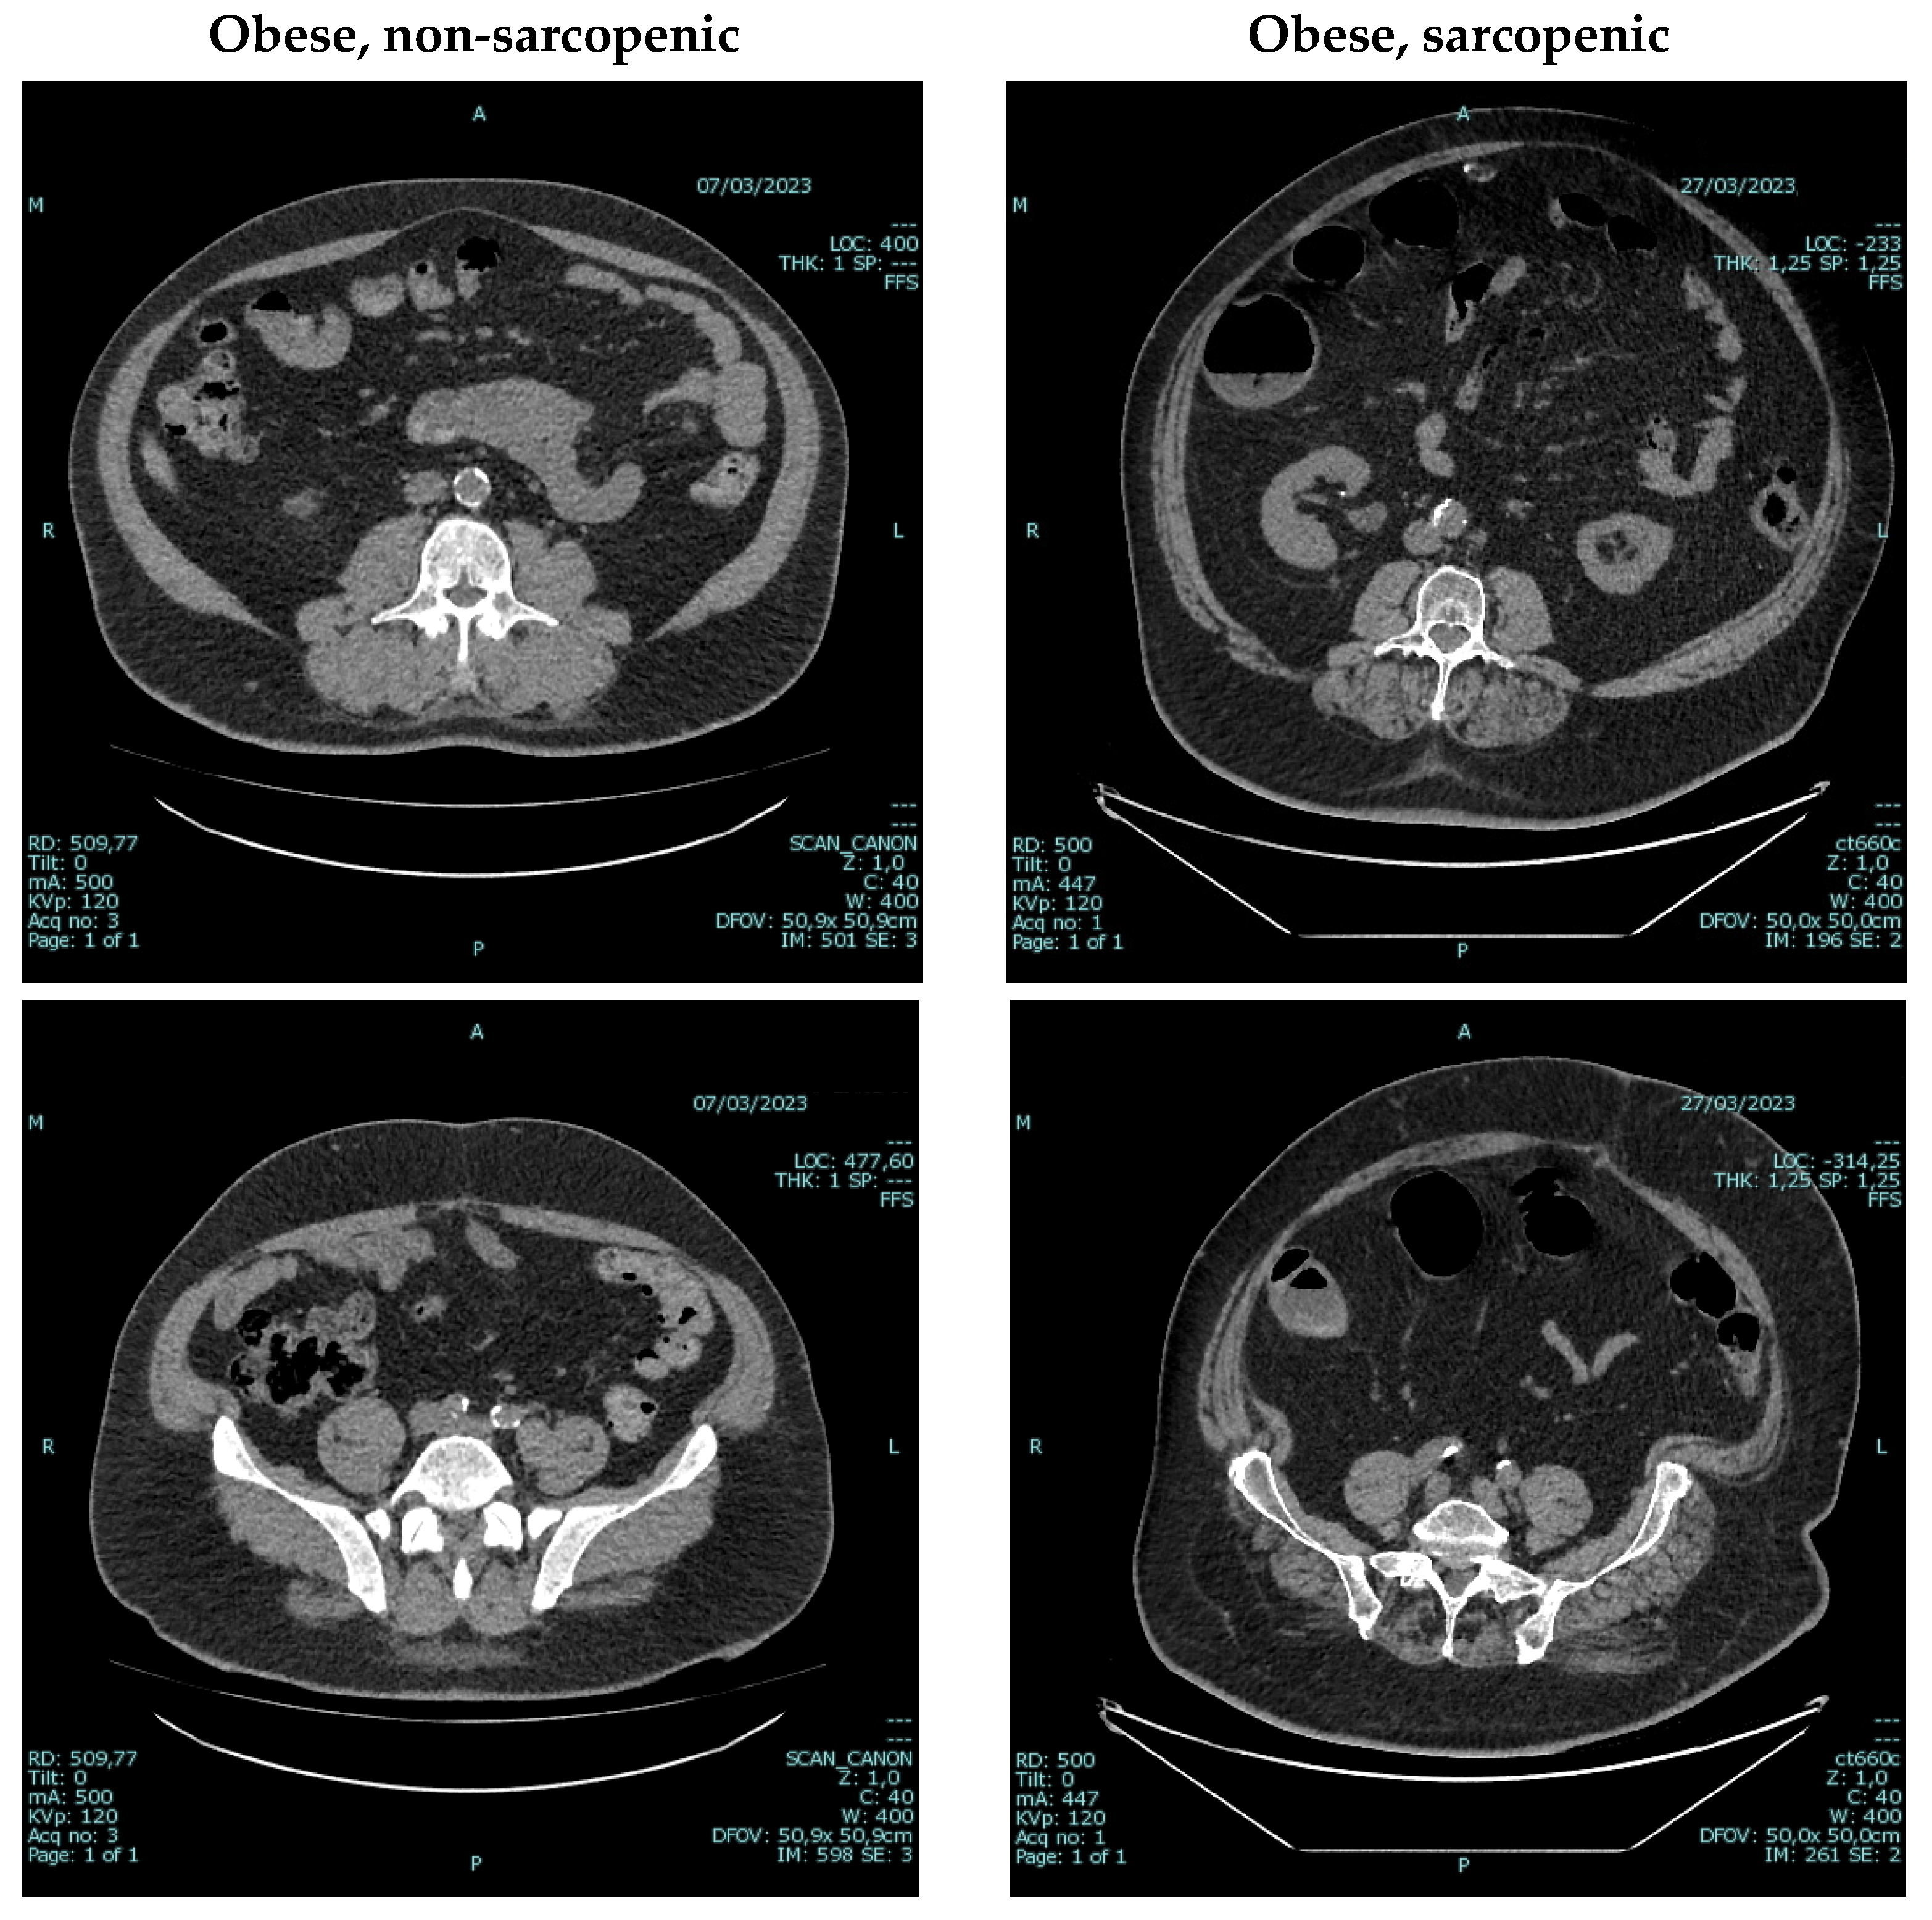

- Bellizzi, V.; Annunziata, G.; Albanese, A.; D’Alessandro, C.; Garofalo, C.; Foletto, M.; Barrea, L.; Cupisti, A.; Zoccali, C.; De Nicola, L. Approaches to patients with obesity and CKD: Focus on nutrition and surgery. Clin. Kidney J. 2024, 17, 51–64. [Google Scholar] [CrossRef]

- Tolonen, A.; Pakarinen, T.; Sassi, A.; Kytta, J.; Cancino, W.; Rinta-Kiikka, I.; Pertuz, S.; Arponen, O. Methodology, clinical applications, and future directions of body composition analysis using computed tomography (CT) images: A review. Eur. J. Radiol. 2021, 145, 109943. [Google Scholar] [CrossRef]

- Donini, L.M.; Busetto, L.; Bischoff, S.C.; Cederholm, T.; Ballesteros-Pomar, M.D.; Batsis, J.A.; Bauer, J.M.; Boirie, Y.; Cruz-Jentoft, A.J.; Dicker, D.; et al. Definition and Diagnostic Criteria for Sarcopenic Obesity: ESPEN and EASO Consensus Statement. Obes. Facts 2022, 15, 321–335. [Google Scholar] [CrossRef]

- Chianca, V.; Albano, D.; Messina, C.; Gitto, S.; Ruffo, G.; Guarino, S.; Del Grande, F.; Sconfienza, L.M. Sarcopenia: Imaging assessment and clinical application. Abdom. Radiol. 2022, 47, 3205–3216. [Google Scholar] [CrossRef] [PubMed]

- Sabatino, A.; Regolisti, G.; Benigno, G.; Di Mario, F.; Avesani, C.M.; Fiaccadori, E. Low skeletal muscle mass by computerized tomography is associated with increased mortality risk in end-stage kidney disease patients on hemodialysis. J. Nephrol. 2022, 35, 545–557. [Google Scholar] [CrossRef] [PubMed]